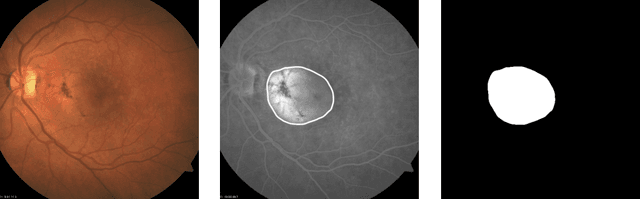

Abstract:Age-related macular degeneration (AMD) is one of the leading causes of irreversible vision impairment in people over the age of 60. This research focuses on semantic segmentation for AMD lesion detection in RGB fundus images, a non-invasive and cost-effective imaging technique. The results of the ADAM challenge - the most comprehensive AMD detection from RGB fundus images research competition and open dataset to date - serve as a benchmark for our evaluation. Taking the U-Net connectivity as a base of our framework, we evaluate and compare several approaches to improve the segmentation model's architecture and training pipeline, including pre-processing techniques, encoder (backbone) deep network types of varying complexity, and specialized loss functions to mitigate class imbalances on image and pixel levels. The main outcome of this research is the final configuration of the AMD detection framework, which outperforms all the prior ADAM challenge submissions on the multi-class segmentation of different AMD lesion types in non-invasive RGB fundus images. The source code used to conduct the experiments presented in this paper is made freely available.

Abstract:This work aims to research an automatic method for detecting Age-related Macular Degeneration (AMD) lesions in RGB eye fundus images. For this, we align invasively obtained eye fundus contrast images (the "golden standard" diagnostic) to the RGB ones and use them to hand-annotate the lesions. This is done using our custom-made tool. Using the data, we train and test five different convolutional neural networks: a custom one to classify healthy and AMD-affected eye fundi, and four well-known networks: ResNet50, ResNet101, MobileNetV3, and UNet to segment (localize) the AMD lesions in the affected eye fundus images. We achieve 93.55% accuracy or 69.71% Dice index as the preliminary best results in segmentation with MobileNetV3.